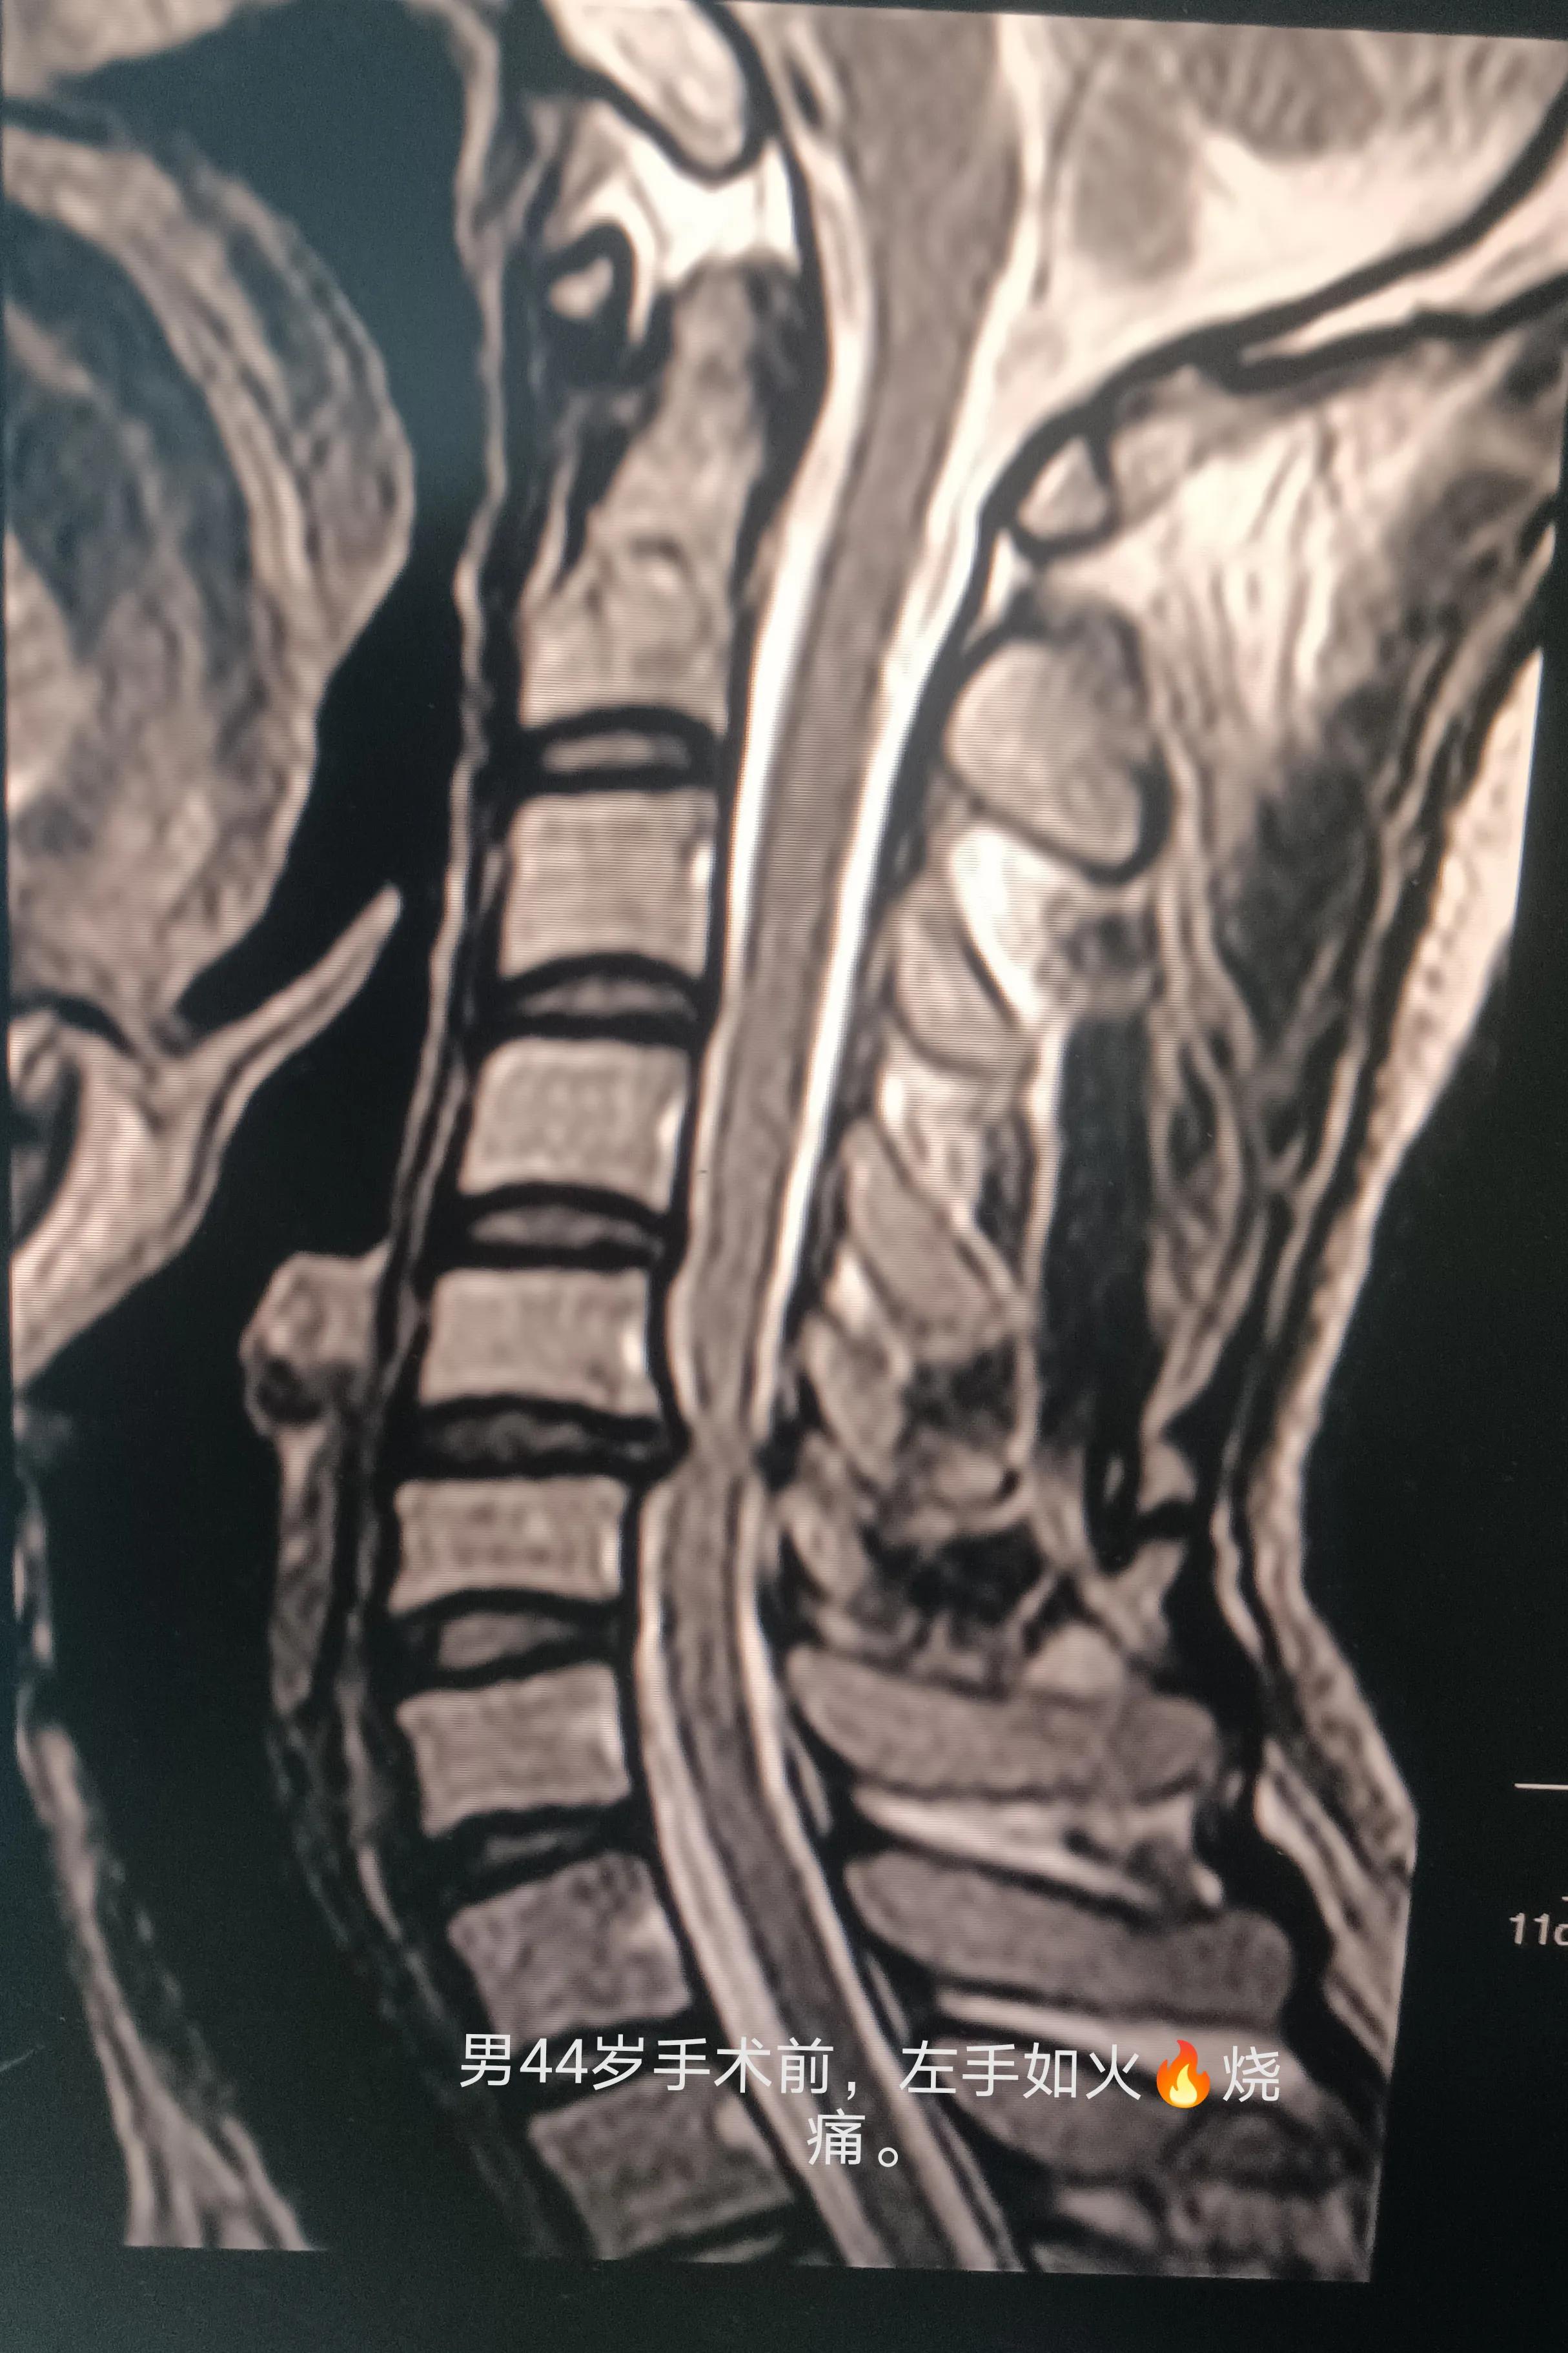

那么怎样能够精确的测试自己有没有颈椎的器质性病变呢?颈椎的器质性病变,包括颈椎生理曲度变直、反弓,椎间盘变性以及椎间盘突出。

一般来说,x光检查,仅仅能发现生理曲度异常,環枢锥对不对称,以及骨质增生,椎间隙是否变窄。cT除了上面的还能发现椎间盘是否突出。MR(核磁)不仅能发现上面所有的病变,还能发现椎间盘是否有变性,而且这项检查没有辐射,上面两项都有辐射。